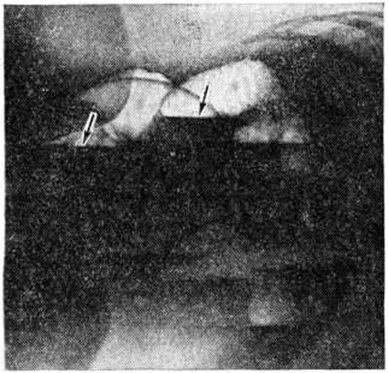

Рис. 2.

Макропрепарат резецированного отдела тонкой кишки при странгуляционной непроходимости: ткани резко малокровны, сдавлены; борозда ущемления указана стрелками.